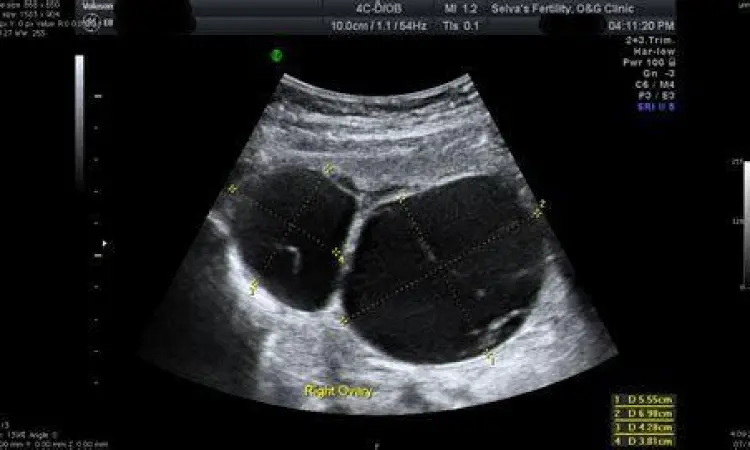

Jika Anda merasakan gejala kista ovarium, dokter biasanya akan melakukan serangkaian tes diagnostik. Langkah pertama adalah pemeriksaan fisik panggul, diikuti oleh ultrasonografi (USG) baik lewat perut maupun transvaginal untuk melihat gambaran kista secara mendetail. Dalam beberapa kasus, tes darah CA-125 mungkin disarankan jika ada kecurigaan ke arah keganasan (kanker), meskipun tes ini tidak selalu akurat karena kondisi non-kanker pun bisa meningkatkan kadarnya.